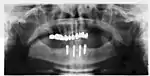

When a more exacting plan is needed beyond clinical judgment, the dentist will make an acrylic guide (called a stent) prior to surgery which guides optimal positioning of the implant. Increasingly, dentists opt to get a CT scan of the jaws and any existing dentures, then plan the surgery on CAD/CAM software. The stent can then be made using stereolithography following computerized planning of a case from the CT scan. The use of CT scanning in complex cases also helps the surgeon identify and avoid vital structures such as the inferior alveolar nerve and the sinus.[31][32]: 1199

Success or failure of implants depends primarily on the thickness and health of the bone and gingival tissues that surround the implant, but also on the health of the person receiving the treatment and drugs which affect the chances of osseointegration. The amount of stress that will be put on the implant and fixture during normal function is also evaluated. Planning the position and number of implants is key to the long-term health of the prosthetic since biomechanical forces created during chewing can be significant. The position of implants is determined by the position and angle of adjacent teeth, by lab simulations or by using computed tomography with CAD/CAM simulations and surgical guides called stents. The prerequisites for long-term success of osseointegrated dental implants are healthy bone and gingiva. Since both can atrophy after tooth extraction, pre-prosthetic procedures such as sinus lifts or gingival grafts are sometimes required to recreate ideal bone and gingiva.